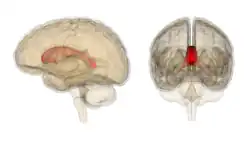

Corpus callosum with anatomography -